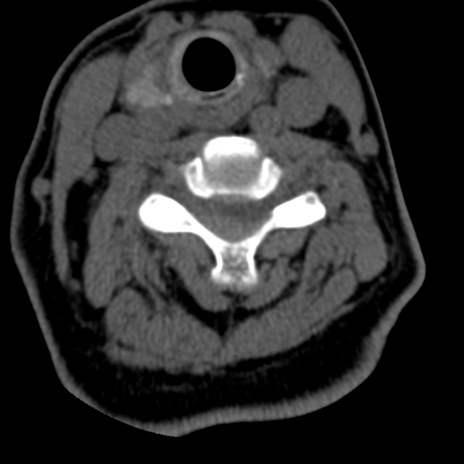

症例50 頚椎CT(横断像)

【症例】60歳代女性

【主訴】後頭部〜右後頸部にかけての痛み

【現病歴】本日飲食店でコーヒーを飲んでいたところ、突然後頭部〜右後頸部にかけて痛みが出現し、右上肢の感覚障害を伴ったため救急要請。

【身体所見】脳神経学的に明らかな異常所見を認めず。右上肢に軽度の感覚障害あり。

異常所見と診断は?

頚椎CT